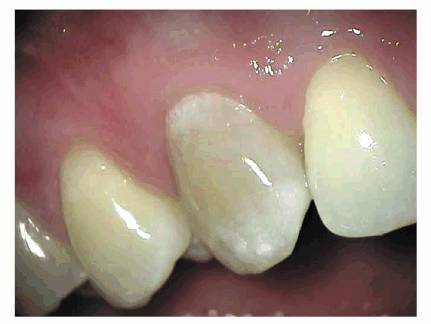

youngster's nonrestored tooth (Figures 19-46A, and 19-46B) would differ considerably from

that of the same tooth with multiple restorations in a middle-aged person (Figures 19-47A, and 19-47B

Figure 19-47A: Access cavities through porcelain-fused-to-metal crowns in a middle-aged male.

Figure 19-47B: Radiograph of the same tooth depicting a narrow root canal. The size of the access opening in the crown reflected the recession of the pulpal complex.